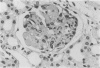

Rabbits given acute serum sickness (ASS) and treated with cyclosporin A (CyA) developed glomerular capillary thrombosis and cortical infarction, lesions not seen in unmodified ASS. Thirty-three NZW rabbits received a single intravenous injection of 250 mg/kg bovine serum albumen (BSA) with or without endotoxin (5 micrograms/kg) on day 0. Groups of rabbits were given intramuscular CyA as follows: 15 mg/kg from day -2 to +8, or 25 mg/kg/day from day -20 to +3 or day 0 to 5. Signs of this renal injury were haematuria, transient proteinuria, glycosuria and oliguria and they occurred during the rapid phase of antigen elimination when immune complexes were being formed. Seventeen of the 33 rabbits developed glomerular capillary thrombi and 11 of 17 also had glomerular and tubular infarction. Electron microscopic examination showed that these lesions were associated with severe endothelial injury and platelet-fibrin-leucocyte thrombi. These changes were more severe in the groups given 25 mg/kg. The lesions were not seen in untreated rabbits and ASS, nor in normal rabbits given equivalent doses of CyA alone. A strikingly similar renal lesion has been seen in patients receiving CyA following bone marrow transplantation, and also in the haemolytic uraemic syndrome. The model we describe may be valuable for the study of the mechanisms of endothelial injury and thrombosis in the kidney.